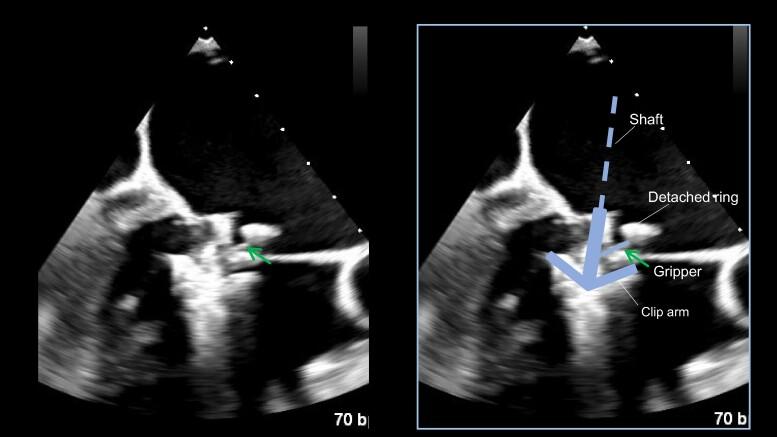

An 89-year-old man underwent mitral valve repair with an annuloplasty ring for moderate atrial functional MR (AFMR). Post-operative transthoracic echocardiography on Day 7 suggested a dislodged mitral annuloplasty ring and recurrent moderate AFMR. However, the MR developed severely, which led to two hospitalizations for congestive heart failure in the past year. Transoesophageal echocardiography (TOE) was performed carefully to ensure that the TEER clip did not interfere with the dislodged annuloplasty ring. Consequently, only the therapeutic target on the medial side of the A2-P2 region was approached posteriorly behind the peri-ring space, without gripper interference.

一名89岁男性因中度心房功能性二尖瓣反流(AFMR)接受二尖瓣瓣环成形术修复。术后第7天经胸超声心动图显示二尖瓣瓣环成形环移位且AFMR复发。然而,二尖瓣反流严重,导致患者在过去一年因充血性心力衰竭住院两次。仔细进行经食管超声心动图(TOE)检查以确保TEER夹不会干扰移位的瓣环成形环。因此,仅在A2-P2区域内侧的治疗靶点在瓣环周围间隙后方经后路处理,未受到夹钳干扰。